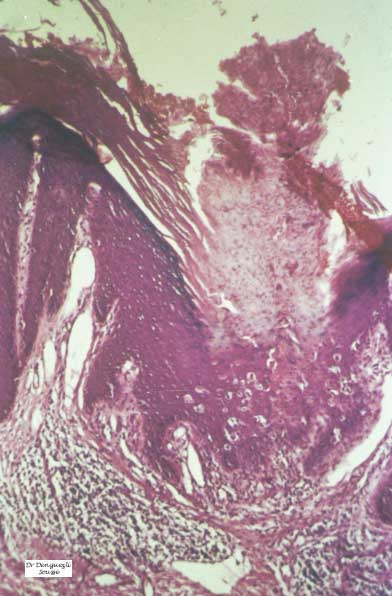

HISTOPATHOLOGY

Histopathologic patterns are similar in all forms of porokeratosis, with the characteristic changes evident at the raised and advancing edge of the lesion. The stratum corneum is hyperkeratotic, with a thin column of poorly staining parakeratotic cells, the cornoid lamella, running through the surrounding normal-staining cells . The underlying keratinocytes are edematous with spongiosis and shrunken nuclei, and a striking dermal lymphocytic pattern may be evident. Underlying the cornoid lamella, the granular layer is either absent or markedly reduced but is of normal

thickness in other areas of the lesion. The epidermis in the central portion of porokeratosis may be normal, hyperplastic, or atrophic. Although characteristic of porokeratosis, the cornoid lamella is not pathognomonic and may also be found in other conditions, such as viral warts, some ichthyoses, and nevoid hyperkeratoses.